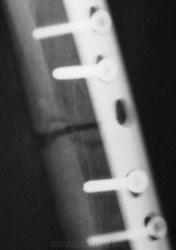

"Удачный" металлоостеосинтез.

Ирония в том, что в проекции четвёртого и последнего шурупов (счет сверху) отломки свёрел, а у второго шурупа отсутствует "шляпка". А в остальном действительно хороший остеосинтез.)))

По поводу "иронии", я не стал встревать, но иллюстрации подготовил давно, и сейчас вставлю. Я согласен с Вами по поводу "шляпки", ну конечно, количество шурупов "впечатляет", ну и поверхности линия перелома, ну прямо "зашлифованные", вопро, вот как срастаться будет.